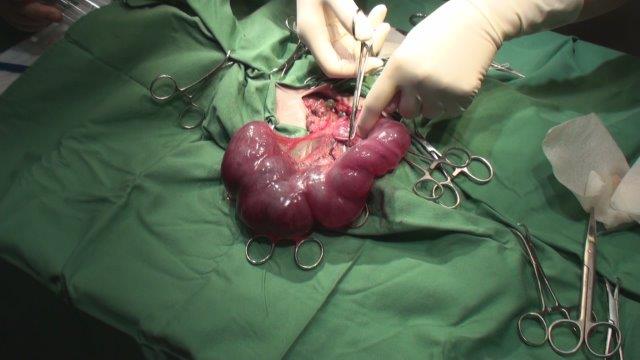

手術中、拡大した子宮がみられる

1.7kg のウサギから369g の子宮が摘出された。左側が腫大している。